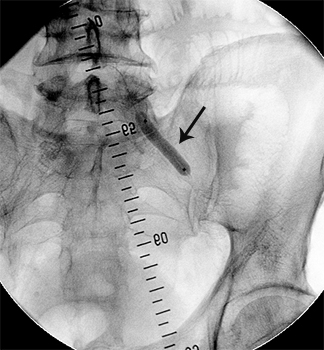

стеноз лівої клубової артерії    балон, роздутий в зоні стенозу    відновлення отвору клубової артерії

Значний стеноз лівої

наружної клубової артерії

Балон-катетер,

роздутий в зоні стенозу

Отвір артерії відновлено на 80%